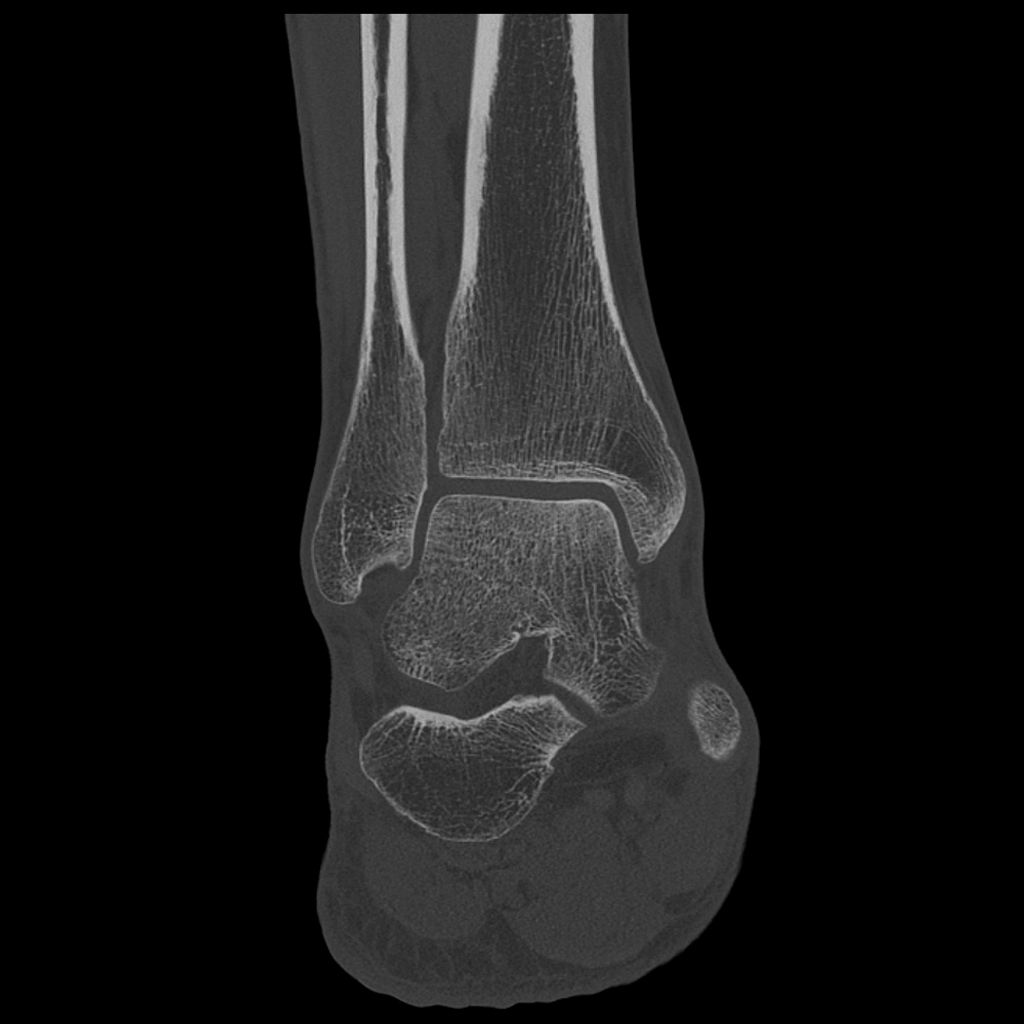

Клінічні приклади

Порівняння звичайної роздільної здатності з ультрависокою роздільною здатністю (УРЗ)²

Звичайна КТ 0,5 мм

КТ з ультрависокою роздільною здатністю 0,25 мм ³